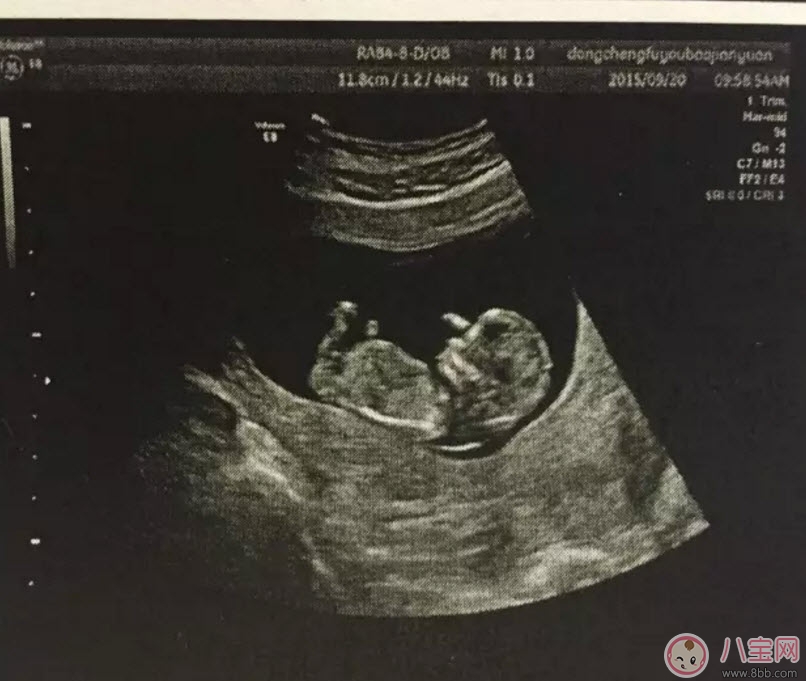

孕早期的時(shí)候用普通B超就可以了,早期只是檢測(cè)胎兒大概情況,比如檢測(cè)是否在宮內(nèi)、胎兒的頭圍、股骨長(zhǎng)、羊水等指標(biāo)。一般在懷孕8-12周做一次黑白B超確定在宮內(nèi)和胎齡。二維B超適用于孕早期。二維B超是最普通的B超,它采用的是黑白超聲診斷技術(shù),即通過(guò)超聲探頭測(cè)得的是黑白圖像,且只能觀測(cè)到胎兒的組織結(jié)構(gòu),測(cè)量出胎兒頭部、身體的長(zhǎng)度,內(nèi)臟、骨骼的大小和形態(tài),以及是否有畸形。

通過(guò)B超能測(cè)出胎兒雙頂徑、頭圍和腹圍等數(shù)據(jù),進(jìn)一步確認(rèn)寶寶的預(yù)產(chǎn)期。還可幫助醫(yī)生觀察胎兒是否存活或有無(wú)畸形,羊水是否過(guò)多等。價(jià)格相對(duì)比較便宜,在90元左右(會(huì)根據(jù)各地具體情況的不同而上下浮動(dòng))。